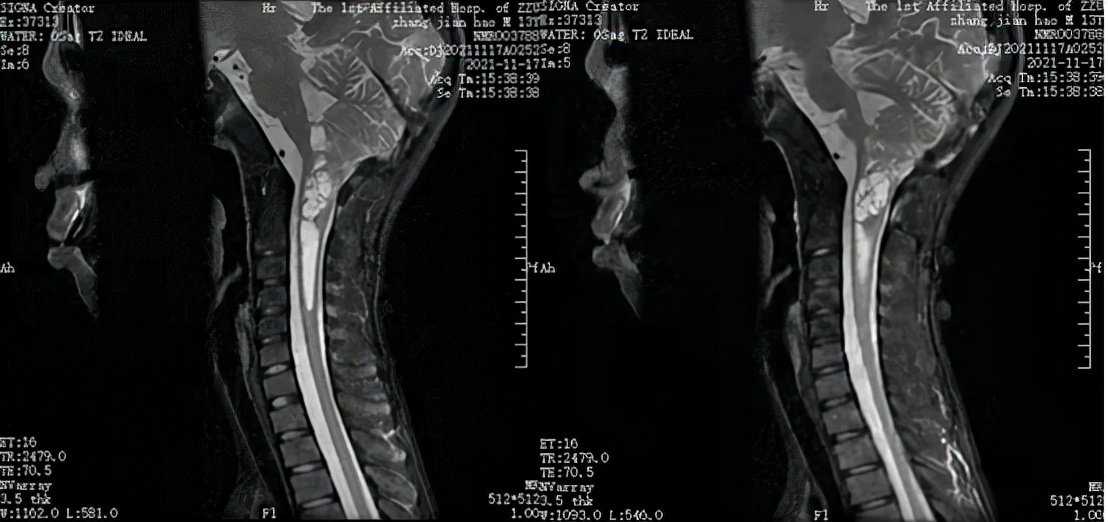

△治疗前(2021-11-17) MRI T2WI 矢状位

△第一周期声动力治疗后(2021-12-18) MRI T2WI 矢状位